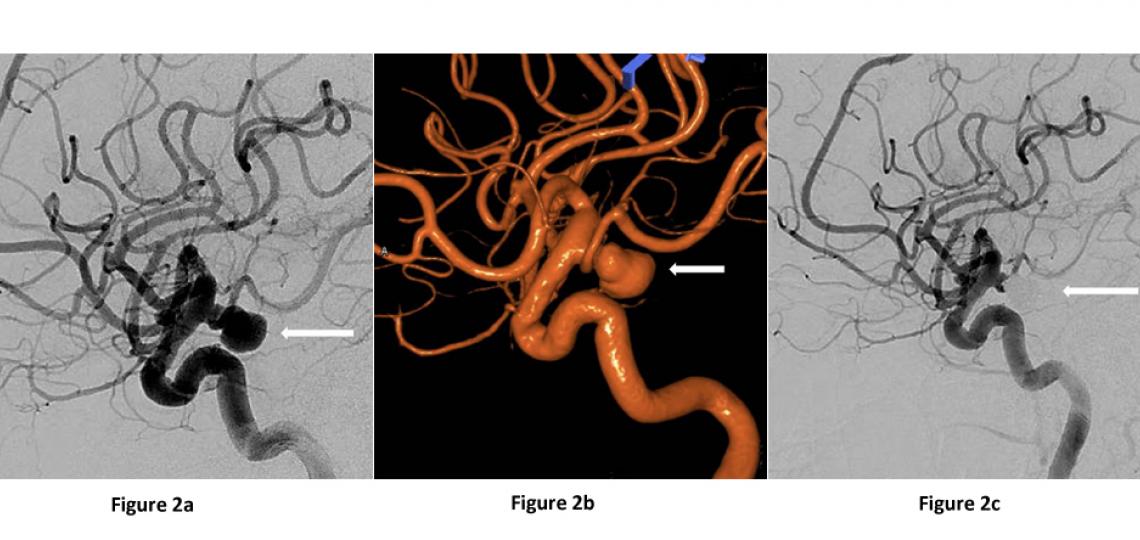

Cerebral Angiogram (Digital Subtraction Angiography) – Small tubes are placed inside the arteries of the leg where they are advanced into the arteries of the neck using x-ray guidance. Dye is then injected through the tube and flows with the blood through the neck arteries into the brain blood vessels. This technique gives doctors the highest quality images of the neck and brain blood vessels (Figures 2a-c).

Figures 2a and 2b: Lateral view of the same ruptured left posterior communicating artery aneurysm (arrow) on a cerebral angiogram before aneurysm treatment. Figure 2c: After treatment with aneurysm coiling.